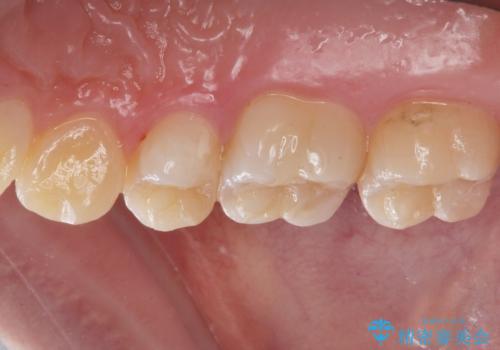

銀歯を白くしたい

- 奥歯の銀の詰め物を白くしたいとのことで来院されました。

- 右上7 セラミックインレー 77,000円費用は治療当時の料金となります

今回は大きな虫歯もなかったため、1回当たり30分程度の治療時間で計2回の来院回数で治療を終えることができました。